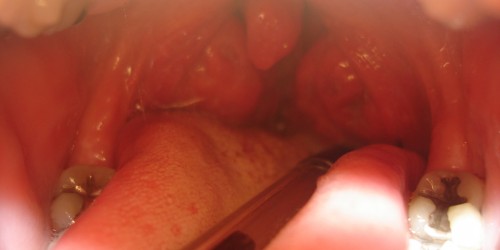

Dysphagia is a medical term for difficult swallowing. The very process of swallowing is quite complex and includes chewing the food and mixing it with saliva, pushing the chewed food into the throat with the assistance of the tongue and finally contraction of the upper pharynx and pushing the food into the lower pharynx and the esophagus. The food eventually reaches the stomach thanks to a peristaltic wave, the specific set of contractions of esophageal muscles.

There are many causes of dysphagia. Esophageal dysphagia, for example, develops due to achalasia, the process of aging, diffuse spasm of the esophagus, esophageal stricture, esophageal tumors and the presence of foreign bodies inside the esophagus. Furthermore, the condition may occur as a consequence of gastroesophageal reflux disease and is also associated with eosinophilic esophagitis, scleroderma and radiation therapy. Oropharyngeal dysphagia results from certain neurological disorders (e.g. Parkinson's disease), neurological damage, pharyngeal diverticula and cancers. And finally, dysphagia in infants and children is generally associated with developmental problems due to premature birth or low birth weight, certain nervous system disorders, cleft palate or cleft lip or it is idiopathic.